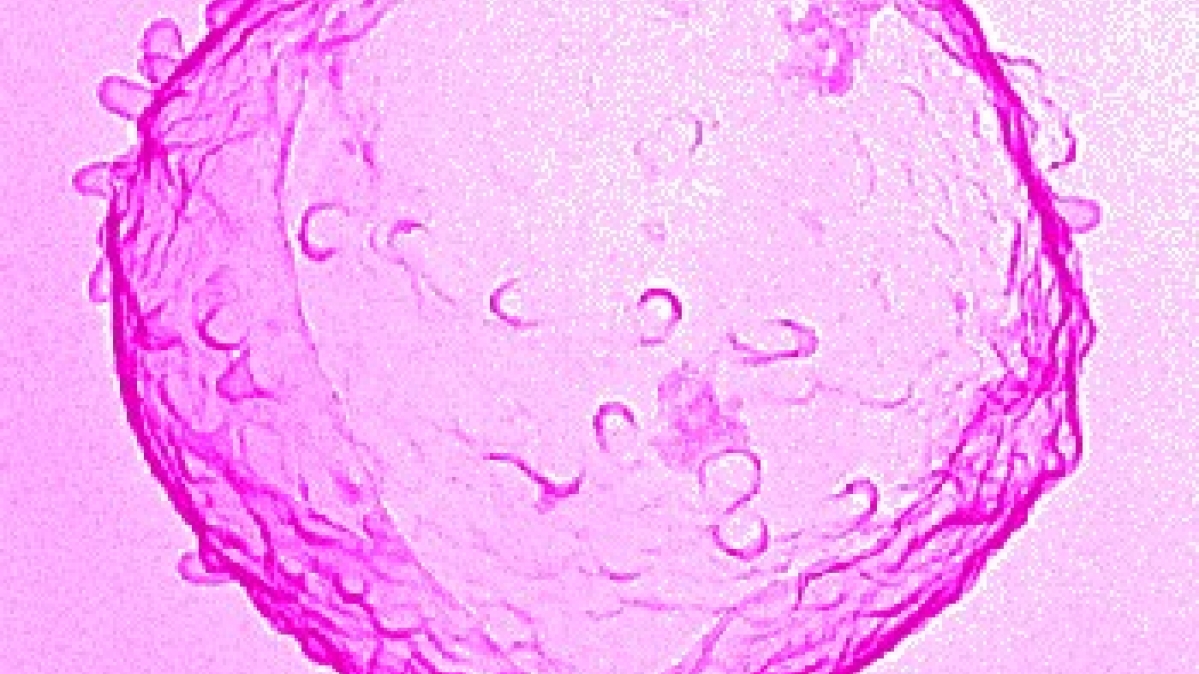

Herpes ist ein Hautausschlag, der mit Bläschenbildung einhergeht. Im engeren Sinn ist es eine Erkrankungen der Haut und Schleimhäute durch Infektion mit verschiedenen Herpesviren, die zum einen → Gürtelrose (Herpes zoster) und zum anderen die Bläschenflechte (Herpes simplex) hervorrufen. Beim Herpes simplex kommt es durch Infektion mit dem Herpes-simplex-Virus meist an den Lippen (Herpes labialis), seltener an der Hornhaut des Auges (Herpes corneae) zu nässendem, brennend-juckendem Bläschenausschlag. Herpes kann aber auch an allen übrigen Übergängen von Haut und Schleimhaut auftreten, z. B. an den Geschlechtsteilen als Herpes genitalis (eine → Geschlechtskrankheit). Wenn sich die stecknadelkopfgroßen Bläschen unter Ausfluss der serösen Flüssigkeit geöffnet haben, trocknen sie ein und heilen nach etwa 10 Tagen narbenlos ab. Der Herpes neigt zu Rückfällen an derselben Stelle, da die Viren meist in den regionalen Nervenknoten (Ganglien) inaktiv erhalten bleiben. Die Erstinfektion findet meist schon im frühen Kindesalter durch Schmier- und Tröpfcheninfektion statt und verläuft meist symptomlos. Der Erreger verharrt in Ruhe (Latenz) vor allem im Nervengewebe und kann wieder aktiv werden, meist bei geschwächter Abwehrlage durch Infektionen, Menstruationsbeschwerden, Magen-Darm-Störungen, Sonneneinstrahlung, Stress u. a. Zur Behandlung dienen austrocknende Puder oder Pasten sowie antivirale Medikamente.